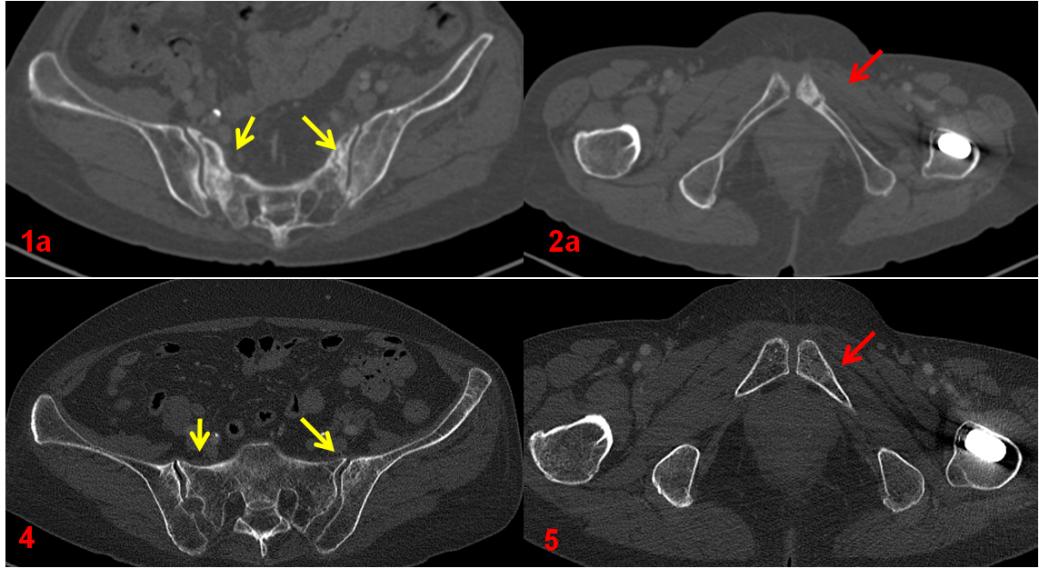

ECT全身骨顯像診斷為機(jī)能不全骨折,建議患者隨診復(fù)查?;颊哂?年后復(fù)查平掃CT及ECT全身骨顯像,綜合兩次影像學(xué)資料,考慮骨折修復(fù)愈合。

復(fù)查CT(圖4、5)對比前片(圖1a、2a)。前片所示骶骨密度不均勻增高(1a,黃箭),本次明顯恢復(fù)(4,黃箭),左側(cè)恥骨骨質(zhì)斷裂(2a,紅箭),本次基本消失(5,紅箭)。